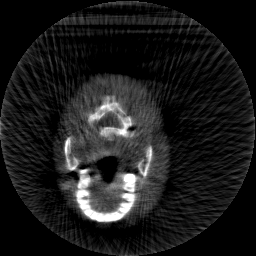

Krylov subspace methods are a powerful family of iterative solvers for linear systems of equations, which are commonly used for inverse problems due to their intrinsic regularization properties. Moreover, these methods are naturally suited to solve large-scale problems, as they only require matrix-vector products with the system matrix (and its adjoint) to compute approximate solutions, and they display a very fast convergence. Even if this class of methods has been widely researched and studied in the numerical linear algebra community, its use in applied medical physics and applied engineering is still very limited. e.g. in realistic large-scale Computed Tomography (CT) problems, and more specifically in Cone Beam CT (CBCT). This work attempts to breach this gap by providing a general framework for the most relevant Krylov subspace methods applied to 3D CT problems, including the most well-known Krylov solvers for non-square systems (CGLS, LSQR, LSMR), possibly in combination with Tikhonov regularization, and methods that incorporate total variation (TV) regularization. This is provided within an open source framework: the Tomographic Iterative GPU-based Reconstruction (TIGRE) toolbox, with the idea of promoting accessibility and reproducibility of the results for the algorithms presented. Finally, numerical results in synthetic and real-world 3D CT applications (medical CBCT and {\mu}-CT datasets) are provided to showcase and compare the different Krylov subspace methods presented in the paper, as well as their suitability for different kinds of problems.